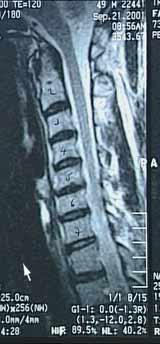

Die Wurzelsyndrome der Halswirbelsäule

Dans le cas d’une hernie discale entre les 5ème et 6ème vertèbres cervicales, c’est la racine nerveuse C6 qui est impliquée. Les déficits suivants peuvent être observés:

Nebenstehend die Gefühlsstoerungen bei den Wurzelsyndromen C7 (Bild 1) und C8 (Bild 2)